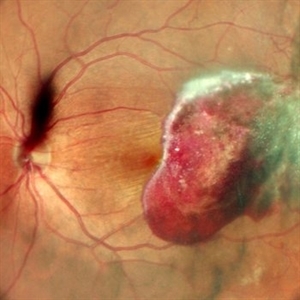

RPE rip in a case of Idiopathic polypoidal choroidopathy RPE rip in a case of Idiopathic polypoidal choroidopathyOct 23 2022 by Anjana Mirajkar, MS Ophthalmology Color photo wide field image in a of 61 year old male with RPE rip in a case of Idiopathic Polypoidal Choroidopathy. Photographer: Dr. Anjana Mirajkar -Retina Foundation, Ahmedabad Condition/keywords: RPE Rip